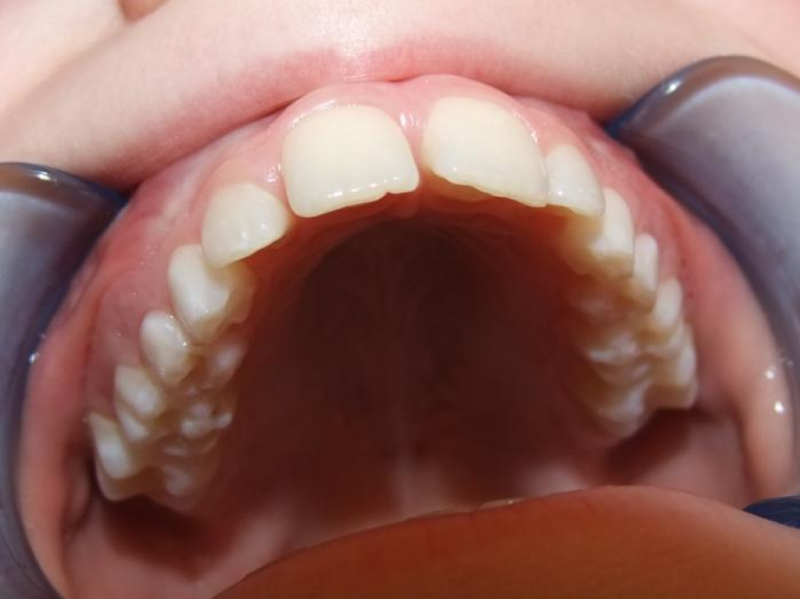

eindfoto

Beschrijving

Leeftijd bij aanvang: 9 jaar

1-6 Bonded Hyrax + volledig vast onderkaak & TransForce

7-13 Twin Block

14-26 volledig vast boven- en onderkaak + TPA

Leeftijd bij retentie: 11 jaar